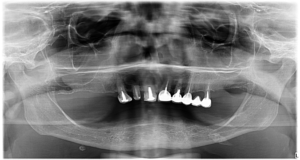

După 20 de ani în care a purtat o proteză parțială și a încercat să își salveze restul dinților, afectați și aceștia, Doamna O. a decis că este timpul să își recapete sănătatea dentară!

În timpul intervenției chirurgicale i-au fost inserate 6 implanturi dentare premium la maxilar și 4 la mandibulă. Apoi, după ce ne-am asigurat că operația s-a vindecat integral, am fixat dantura finală din Zirconiu pe o structură din Titan.